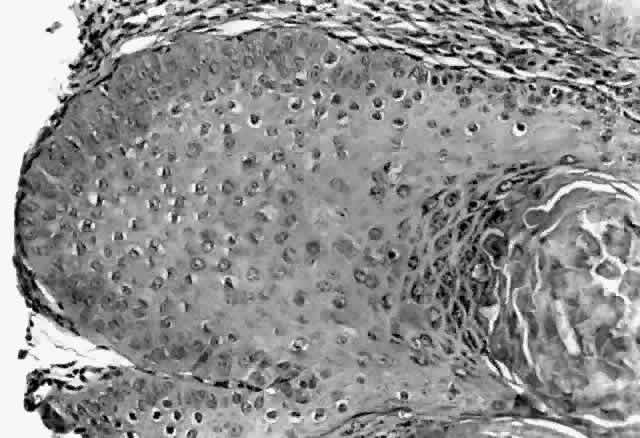

HPV-induced conjunctival squamous papillomas demonstrate papillomatosis, acanthosis, and koilocytosis (Fig. 6). Because they are mucous membrane lesions, those of the conjunctiva and lacrimal sac show no granular cell layer but will show keratinization if they are large or exposed (Fig. 7). In our experience the frequency of koilocytes is variable, even in lesions almost certain to be viral (Fig. 8). Scattered inflammatory cells may be present in the cores or epithelium. Virus can be detected immunohistochemically in the nuclei of the cells (Fig. 9).

Fig. 6. Eyelid papilloma, histology. High-power view of acanthotic epithelium and koilocytes. (Original magnification × 400)